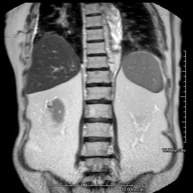

- RM d'Abdomen

Prova diagnòstica no invasiva que consisteix en l'obtenció d'imatges d'alta definició anatòmica de l'abdomen mitjançant l'ús d'un camp electromagnètic i ones de ràdio (amb un emissor i un receptor). No utilitza radiació ionitzant. En aquesta exploració s'inclouen el fetge, el pàncrees, la melsa, la via biliar, la vesícula biliar, les glàndules suprarenals, els ronyons, l'aorta abdominal, la vena cava inferior, l'estómac, el duodè, etc. En alguns casos caldrà emprar contrast paramagnètic (Gadolini) per caracteritzar les lesions. - RM Pelvis femenina